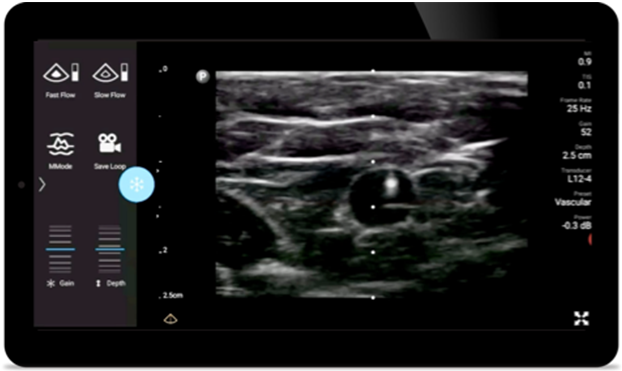

Снижение частоты осложнений при интервенционных процедурах

Портативная ультразвуковая система Lumify для анестезиологии поможет четко визуализировать нервы, сосуды, фасции и границы при размещении иглы.